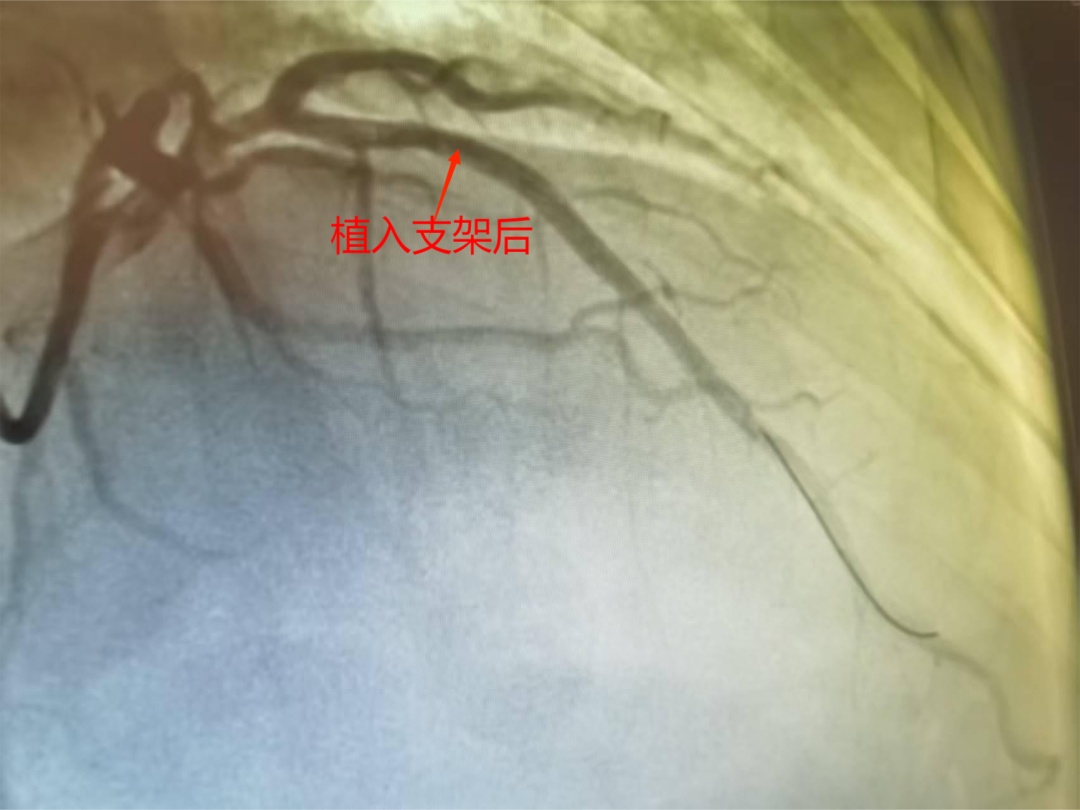

支架植入术后血管狭窄消失

术后,患者胸痛症状完全消失,生命体征平稳,顺利康复出院。此次手术的成功,意义非凡,不仅切实为患者解除了病痛折磨,更为其带来了极大便利。患者及家属无需再长途跋涉前往重庆市大医院,在家门口就能享受到与市级医院同等高效、优质的医疗服务,就医负担得以大幅减轻。